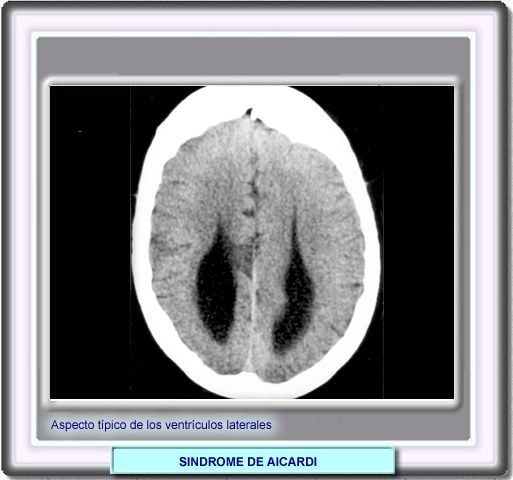

Como consecuencia de la agenesia total o parcial del cuerpo calloso, los ventriculos laterales toman un aspecto caracteristico de "cuernos"